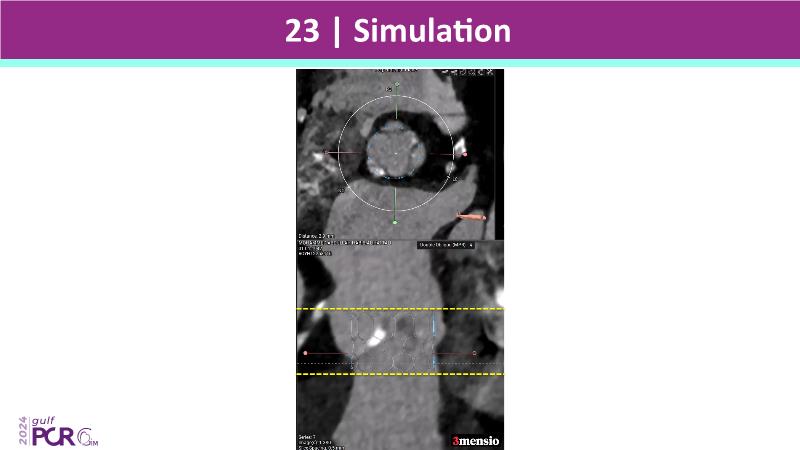

Stay ahead in TAVI innovation by exploring the advanced balloon-expandable Myval THV series. This session highlights the latest clinical data, optimal sizing and implantation techniques, and valuable real-world insights, including long-term follow-up results.

- To understand the best practices for Myval sizing and implantation technique for best outcomes